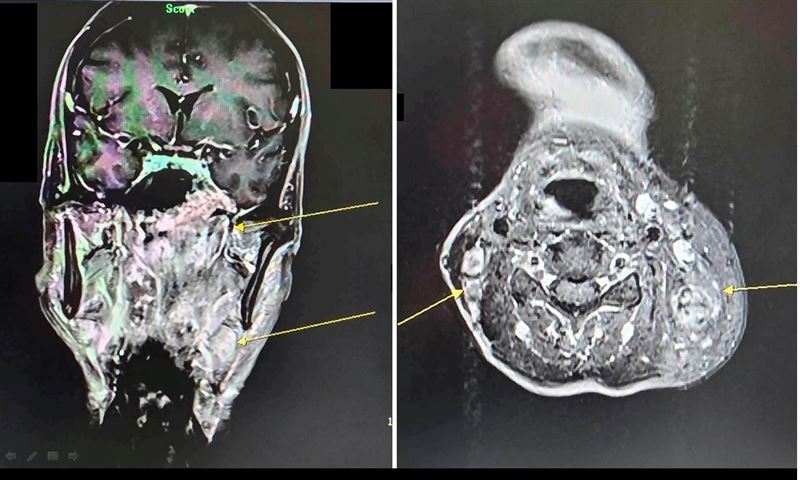

病人透過核磁共振檢查,確診為鼻咽癌(黃色箭頭處)。(圖/大千綜合醫院提供)

很多人以為耳鳴只是過勞或耳朵發炎,但這可能是身體發出的癌症警報!50歲的林先生因左耳持續耳鳴且聽力下降,原以為只是單純聽力變差,前往耳鼻喉科檢查。沒想到,經鼻咽內視鏡檢查,竟發現鼻咽部有腫瘤,轉介至大千綜合醫院進一步核磁共振檢查後,確診為鼻咽癌第三期,且癌細胞已轉移至頸部淋巴。所幸,經大千癌症醫療團隊治療後,追蹤至今三年多病情控制良好,無復發或轉移的情形。